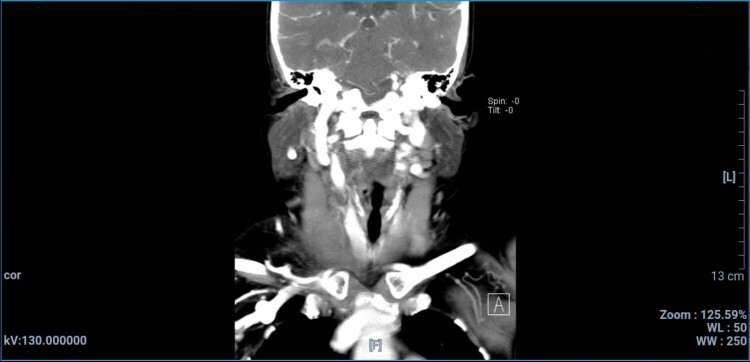

Lemierre's syndrome is marked by presence of septic thrombophlebitis in the internal jugular vein. This case report describes a 57-year-old woman who presented with a progressively swelling neck with onset 1 day prior to admission. She had a history of untreated dental infection. Physical examination revealed slightly increased blood pressure, at 140/80 mmHg, and a painful, erythematous, warm swelling in the mid area of the neck. Ultrasound of the neck revealed occlusive intraluminal thrombus in the right internal jugular vein, a computed tomography (CT) scan with contrast showed that there was a blockage in the right jugular vein. The mainstay treatment for Lemierre's syndrome is antibiotics, while administration of anticoagulants remains controversial. The patient was treated conservatively, with administration of antibiotics and anticoagulant. Several days later the patient's condition had improved significantly, with less pain and reduced swelling.

Abstract Image